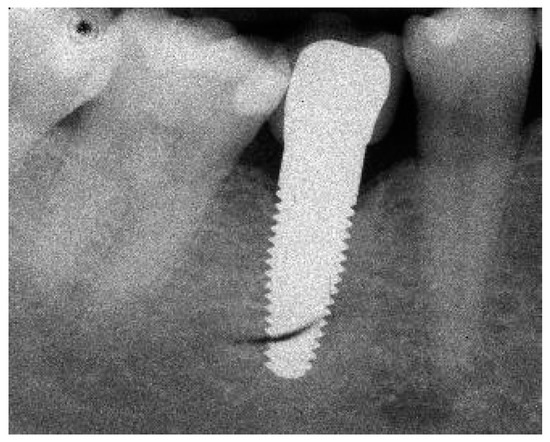

Radiograph of the perimplant bone situation before crown cementation.

Figure A3.

Radiograph of the perimplant bone situation at the 1-year follow-up.

Figure A6.